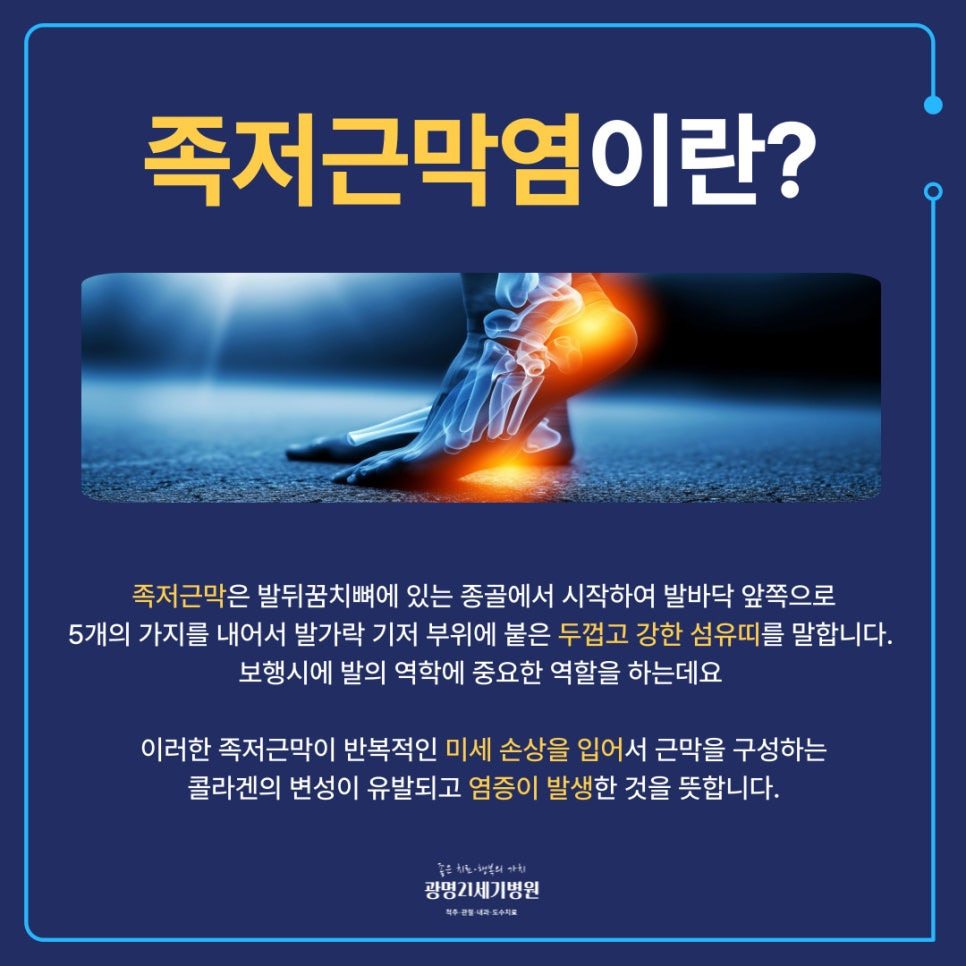

족저근막은 발뒤꿈치뼈에 있는 종골에서 시작하여 발바닥 앞쪽으로 5개의 가지를 내어서 발가락 기저 부위에 붙은 두껍고 강한 섬유 띠를 말해요. 이는 발의 아치 형태를 유지하고 발바닥에 가해지는 충격을 흡수하는 완충작용은 물론 체중이 실린 상태에서 발을 들어 올리는 데 도움을 주어 보행 시 발의 역학에서도 중요한 역할을 해요.

족저근막은 두껍고 질기지만 과도하게 사용하거나 충격에 의해 손상된다면 염증이 발생할 수 있는데 이때 발뒤꿈치부터 발바닥 전반으로 통증이 생기는 질환을 족저근막염이라고 해요.